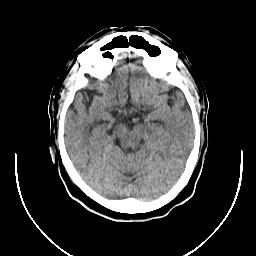

CT Study #1 -- Slice #10